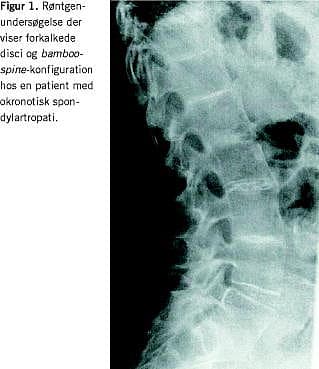

En 53-årig kvinde blev på mistanke om AS henvist til reumatologisk ambulatorium. Problemet var tiltagende smerter og stivhed i ryggen samt radiologiske forandringer i SI-leddene. Smerterne var uden inflammatorisk præg (ingen morgenstivhed og ingen bedring ved aktivitet). Hun rapporterede misfarvning af urin og sved. Patienten var i øvrigt rask. Tyve år tidligere var hun blevet kolecystektomeret på grund af recidiverende galdestensanfald. Klinisk fandt man svært nedsat bevægelighed i columna thoracolumbalis og tegn på artrose i knæleddene. Ørebrusken var gråsort pigmenteret, mens sclerae var upåfaldende. Der var normal hjertestetoskopi. Røntgenundersøgelse af columna og pelvis viste udbredt højdereduktion og udtalte forkalkninger af disci, sklerosering af tilstødende terminalplader af corpora og bamboo-spine -konfiguration lumbalt (Figur 1 ). Der var sklerosering og småerosive forandringer omkring åbentstående SI-led bilateralt, og i symfysen var der afsmalnet ledspalte, små subkondrale cyster og subkondral sklerosering. Hofteleddene var uden artrose. Røntgenundersøgelse af knæleddene viste udtalt artrose femorapatellart og -tibialt. En urinprøve blev ikke med sikkerhed misfarvet efter henstand. Almindelig blodprøvescreening viste normale forhold. Der kunne påvises homogentisinsyre i urinen. Patienten fik stillet diagnosen okronose og blev afsluttet med paracetamol og ibuprofen .

Symptomerne er smerter og stivhed i led og ryg. Ved røntgenundersøgelse af de vægtbærende led ses degenerative forandringer med afsmalnede ledspalter og subkondral sklerosering (okronotisk artropati). Ved okronotisk spondylartropati (OSpA) er columna afficeret, særlig toracolumbalt. Der ses svære discusdegenerationer ofte med ossifikation af nuclei pulposus samt andre degenerative forandringer. Kombineret discusdegeneration og -resorption fører til ankylose. Sekundær knoglenydannelse med udvikling af intervertebrale knoglebroer kan give et bamboo-spine -lignende billede. Ved involvering af sacroiliacaleddene (SI-leddene) ses subkondral sklerosering, men aldrig aflukning af leddene. Symfysen kan også være sæde for forandringer. Forandringerne i det aksiale skelet kan til forveksling ligne dem, man ser ved andre spondylartropatier, herunder AS, spondylose og diffus idiopatisk skeletal hyperostose (DISH). Værdien af magnetisk resonansskanning er uafklaret. Sjældent optræder kalcifikation af aortaklapperne. Nyre-, galde- og prostatasten er beskrevet. Ekstraskeletale manifestationer i form af entesopati, uveit, hud- og slimhindeforandringer forekommer ikke. Påvisning af homogentisinsyre i serum og urin er diagnostisk for alkaptonuri. Biokemien er i øvrigt normal. Behandlingen er symptomatisk [1-5].